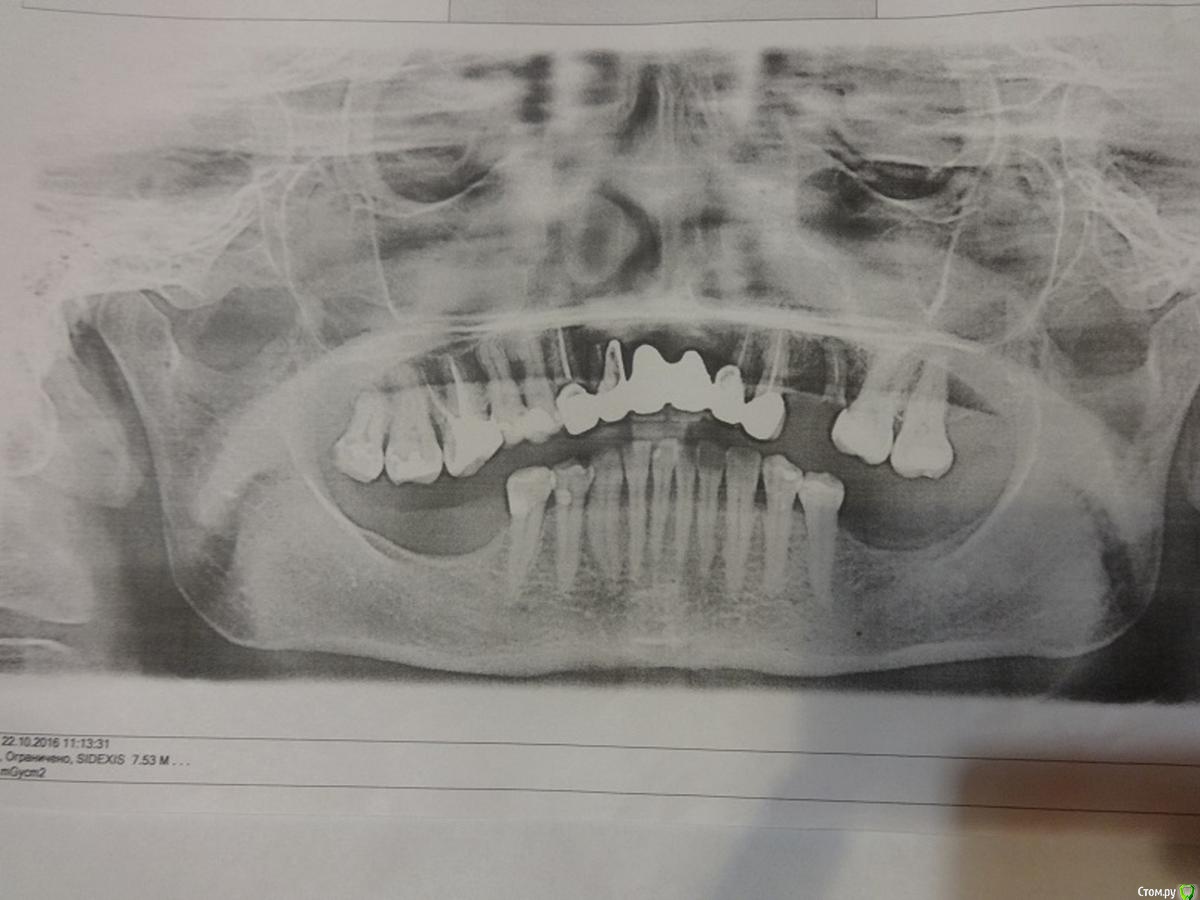

Добрый день. Прошу совет. Возраст 54 года.

Посоветуйте как мне быть дальше? Пролечила кариес и переделала старые пломбы (снимок до лечения) - даже 8ка нашлась, думала, что все давно поудаляла :).

У меня на верхней челюсти стоит мост из металлокерамики 6 зубов с 13 по 23 делали в 2000 г. Отсутствовали обе единицы. Протезировала несколько раз с 19 лет, была резекция верхушки зуба с кистой сначала одного, потом другого. Затем удалила корни и была попытка наращивания кости гранулами, но прошла неудачно - материал не прижился и от имплантации пришлось отказаться. В итоге, согласилась на мост из МК, но врач настоял на том, чтобы не потерять через некоторое время опорные двойки ставить мост и на клыки. До сих пор жалею, что депульпировала и обточила 4 зуба, чтобы закрыть дыру их двух :(

15 остался корень - сломалась МК коронка на штивте или вкладке (?) - планирую имплантацию одновременную с удалением корня, наверно в данном случае это лучше, чем удалить корень и ждать заживления и только потом ставить имплант.

На нижней челюсти отсутствую жевательные зубы 6,7,8 с обеих сторон и очень давно. Совсем не хочется съемный вариант. Понимаю, что кость атрофировалась в это месте. Есть ли шанс поставить импланты?